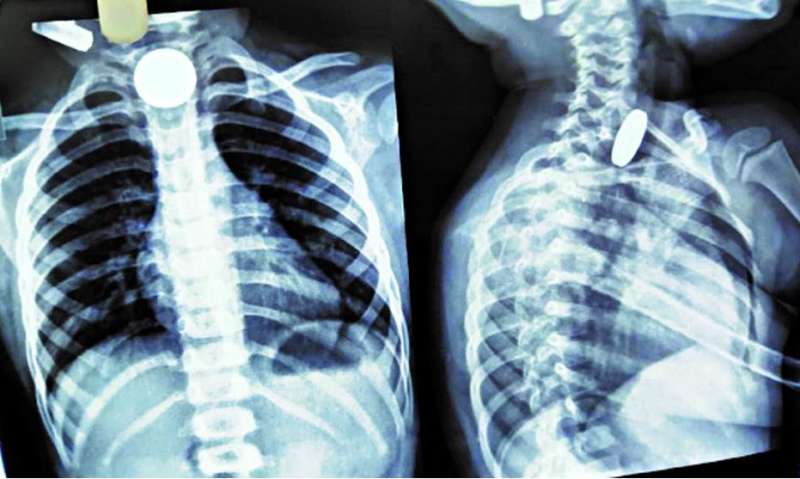

खिलौना नहीं सिक्का था! बच्चे ने निगले 5-10 रुपये के सिक्के, डॉक्टरों ने ऑपरेशन कर निकाले

बच्चे को बुधवार देर रात 11 बजे इमरजेंसी में उपचार के लिए लाया गया। बच्चे की एक्सरे जांच में तीन सिक्के खाने की नली में फंसे दिखे। उपचार के लिए तुरंत बच्चे को ऑपरेशन थियेटर लेकर गए। डॉक्टरों की टीम ने एनेस्थीसिया देकर एसोफैगोस्कोपी प्रक्रिया के जरिए सिक्के बाहर निकाले। इसमें दो पांच रुपये के सिक्के और एक दस रुपये का सिक्का शामिल था।